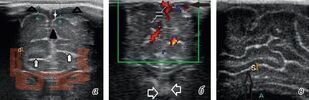

Учебное пособие посвящено вопросам организации и проведения нейровизуализационной диагностики у детей при энцефалитах и менингитах на различных этапах заболевания. В книге указаны особенности визуализации энцефалитов в зависимости от этиологии и тяжести течения заболевания.

Мы приводим разбор возможностей диагностических методик и усовершенствованный алгоритм нейровизуализационной диагностики при нейроинфекциях у детей.